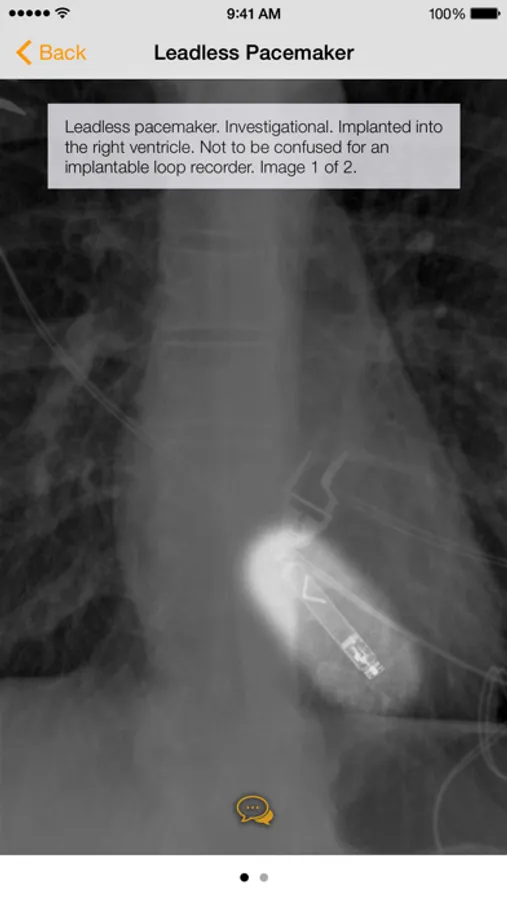

· Countless images, organized into the following categories: Common Cardiac Conduction Devices, Less Common Cardiac Conduction Devices, Vascular Devices, Airway Devices, Enteric Devices, Neurological Devices, Musculoskeletal Devices, and Miscellanenous Devices.

· Tap the caption icon to read more about the device and to see it highlighted on the chest radiograph.